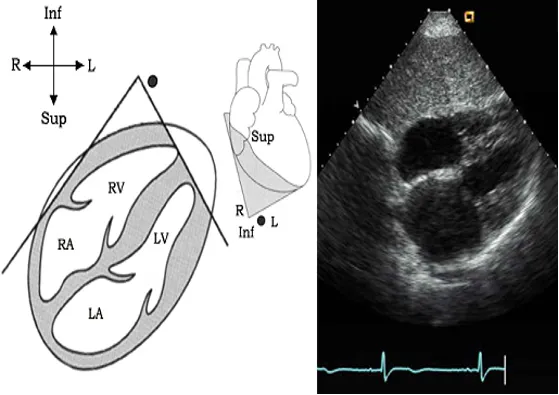

剑突下四腔心切面

探头位置:探头位于剑突下声速指向左肩。

观察内容:4个房室腔;二尖瓣、三尖瓣、房间隔、室间隔。